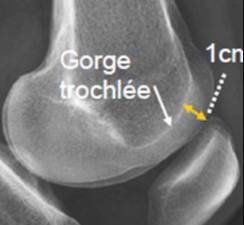

Profondeur trochléenne

- Normal >5mm